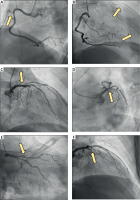

Figure 3

Coronary angiography findings of coronary three-vessel disease. A – The right coronary artery (RCA) showing stenosis of the right ventricular branch (arrow). B – Retrograde perfusion of the occluded left anterior descending artery (LAD) through collateral circulation via the RCA (arrows). C – Stenosis of the distal left main coronary artery (arrow). D – Complete occlusion of the proximal LAD. E, F – Occlusion of the LAD confirmed in a different angiographic projection